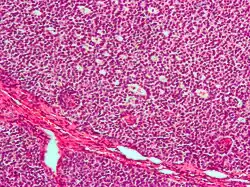

Micrograph of a granulosa cell tumour, a type of sex-cord–gonadal stromal tumour. H&E stain.